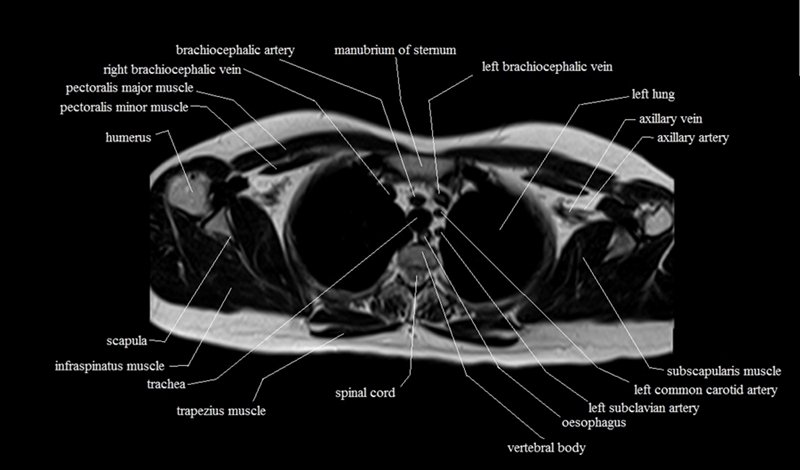

MRI Axial Cross Sectional Anatomy of Chest

This MRI chest (thorax) axial cross sectional anatomy tool is absolutely free to use. Use the mouse scroll wheel to move the images up and down, or alternatively, use the tiny arrows (→) on both sides of the image to navigate through the images. For a more detailed view, double-click the image to view it in full screen, and use the menu in the top right-hand corner to view individual slides or play them in a loop.